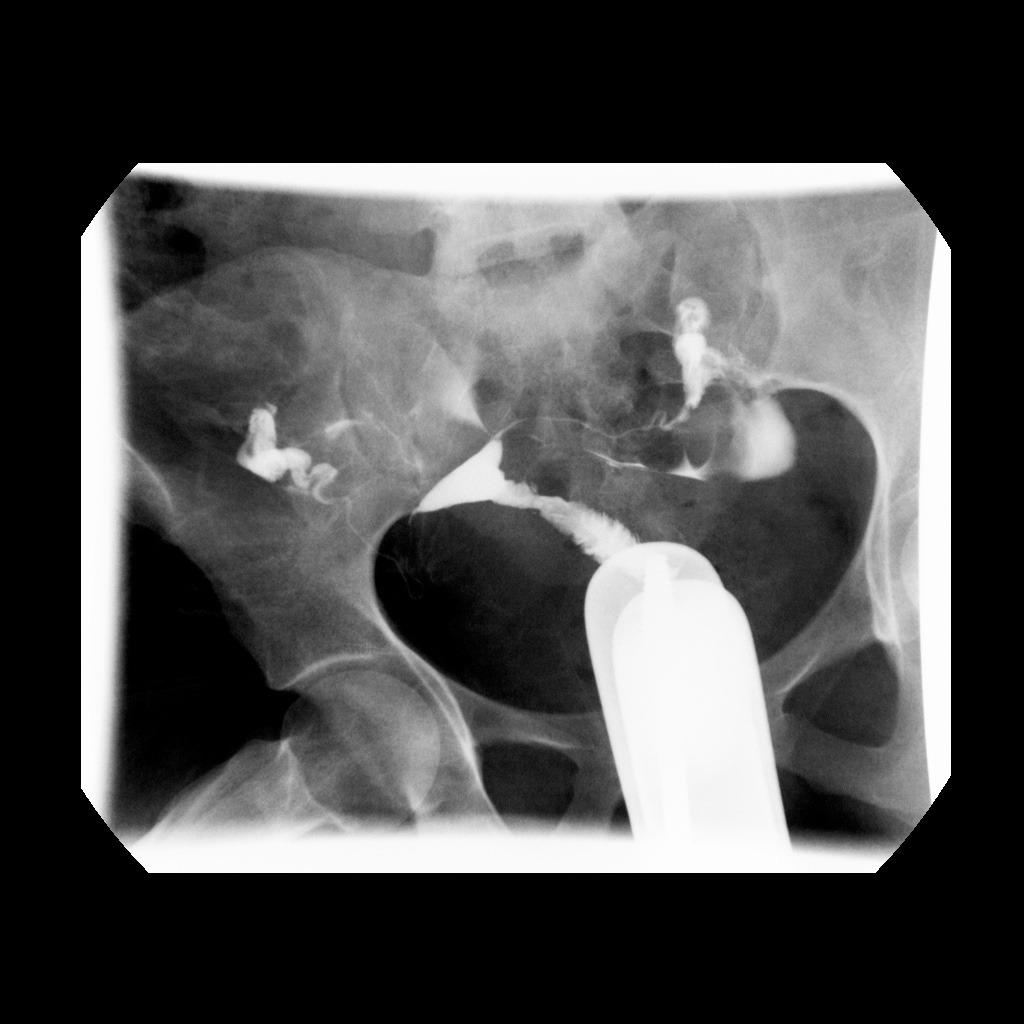

- Gynaecological examination: Hysterosalpingogram(HSG) – to view patency of fallopian tubes for infertility workup